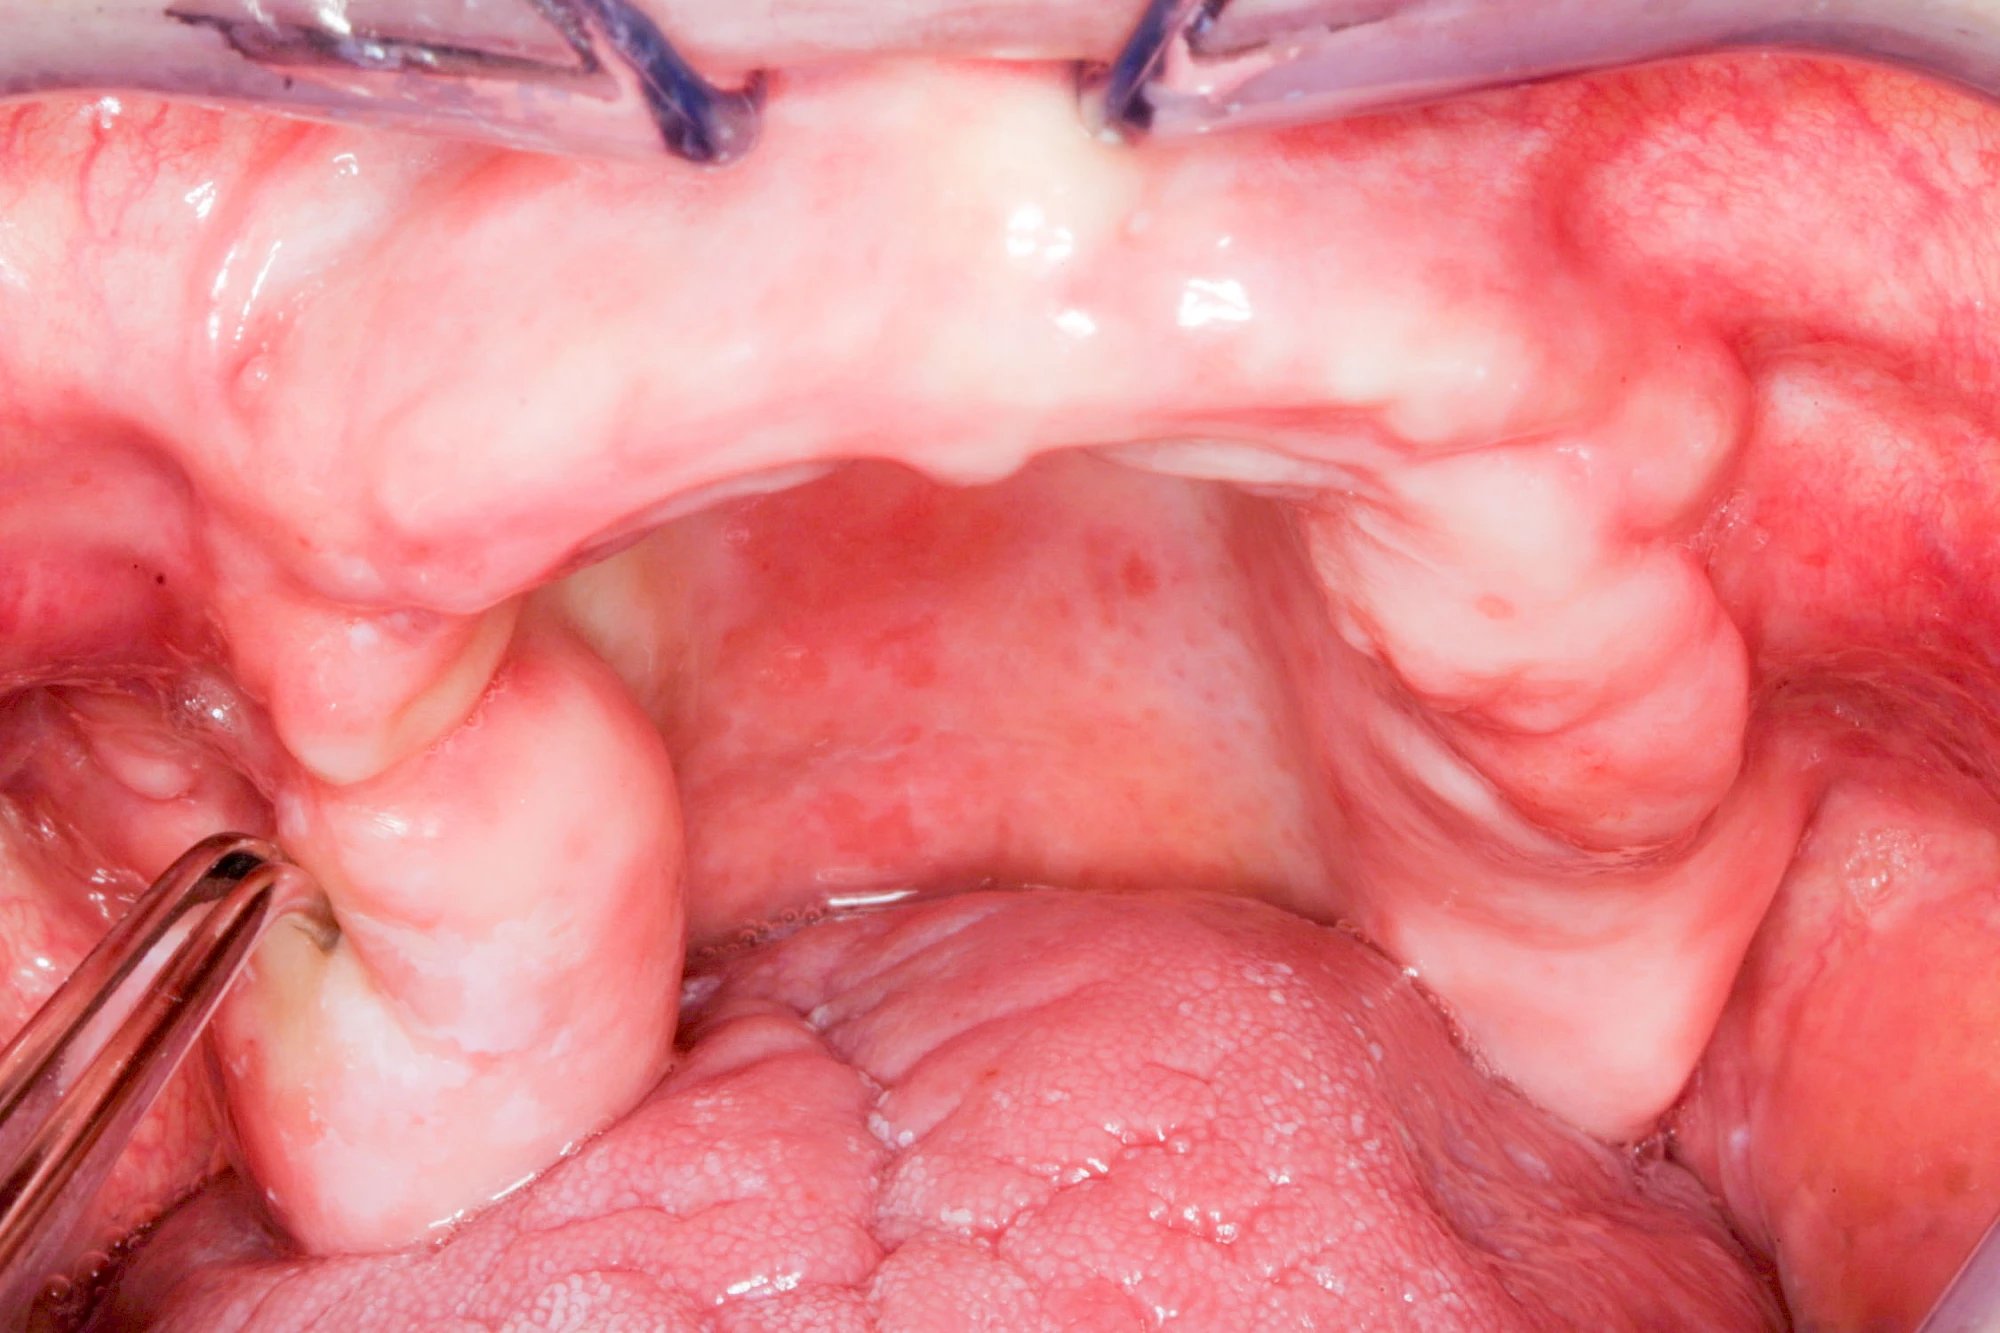

Lippen-Kiefer-Gaumenspalte

Lippen-Kiefer-Gaumenspalten (LKG-Spalte) sind angeborene Fehlbildungen im Mund-Kiefer-Gesichtsbereich. Die Gewebestrukturen im Bereich des Oberkiefers sind im Zuge der Entwicklungen bis zur Geburt nicht zusammengewachsen. Diese Fehlbildung zählt zu den häufigsten Fehlbildungen des Menschen, von 500 Neugeborenen ist eines betroffen. Die Fehlbildungen können sich auf Lippe, Gaumen und Kiefer allein beschränken, treten häufig aber kombiniert und in seltenen Fällen sogar beidseits auf.

Heute werden in Deutschland Menschen mit Lippen-Kiefer-Gaumenspalten bereits ab Geburt von Experten verschiedener Fachrichtungen (Mund-Kiefer-Gesichtschirurgen, Kieferorthopäden, Logopäden) betreut, damit entsprechende Korrekturen schon frühzeitig erfolgen können. Gerade jedoch bei älteren Menschen ist dies nicht immer geschehen. Diese Menschen tragen häufig technisch aufwendige Zahnprothesen.